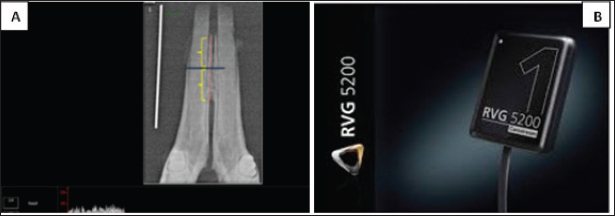

Digital radiographical measurement

Digital radiographic assessment was performed using Carestream Imaging Software (v7.0.3) to evaluate bone density in the para-symphysis region of the right mandibular cancellous bone between the alveolar crest and bifurcation. Measurements were expressed in gray values (0–255 GV) and analyzed using standardized coronal and apical reference points (Pollard and Phillips, 2017). Radiographic recordings employed a size 1 dental digital sensor (RVG 5200, Carestream Dental LLC).

The jaw sample was placed on the sensor with its lingual part touching the sensor surface sleaved and the cone of the dental X-ray machine (Getidy intraoral X-ray system, tube). The source image distance was about 20 cm so that the central ray directed in perpendicular direction to sample surface which was parallel to sensor surface that in contact with it. Tube model K 127-0.8-70, settings were 70 kv and 7 mA with exposure time 0.30 as in Figure 5A and B. Radiographic bone density assessment is shown in Figure 4.

Fig. 4. (A): digital bone density assessment of target area of the rabbit mandibular jaw. (B): RVG 5,200 dental sensor (size 1); TROPHY,4, rue F. pelloutier, Croissy-Beabourg, 77,435 Marne La Vallee Cedex 2, France Carestream Dental LLC, Cumberland Boulevard, Suite 700, Atlanta, GA USA.